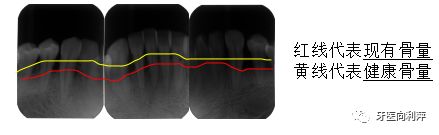

健康状态下,我们的牙槽骨在釉牙骨质界下方2mm的位置,即下图中黄线的位置,而牙周炎患者会出现不同程度的“水土流失”,如下图中红线的位置所示,“水土流失”严重的情况下,牙齿则会出现松动。因此,及时去除牙齿周围的牙石等刺激物是十分必要的,如果你为了“所谓的美观”,任由牙石侵占领土,待疾病发展到后期时,不仅花费更高,而治疗效果也更差,所谓千金难买一笑。因此,早发现、早诊断、早治疗非常重要,您的牙齿将由您自己和口腔医生共同来守护。